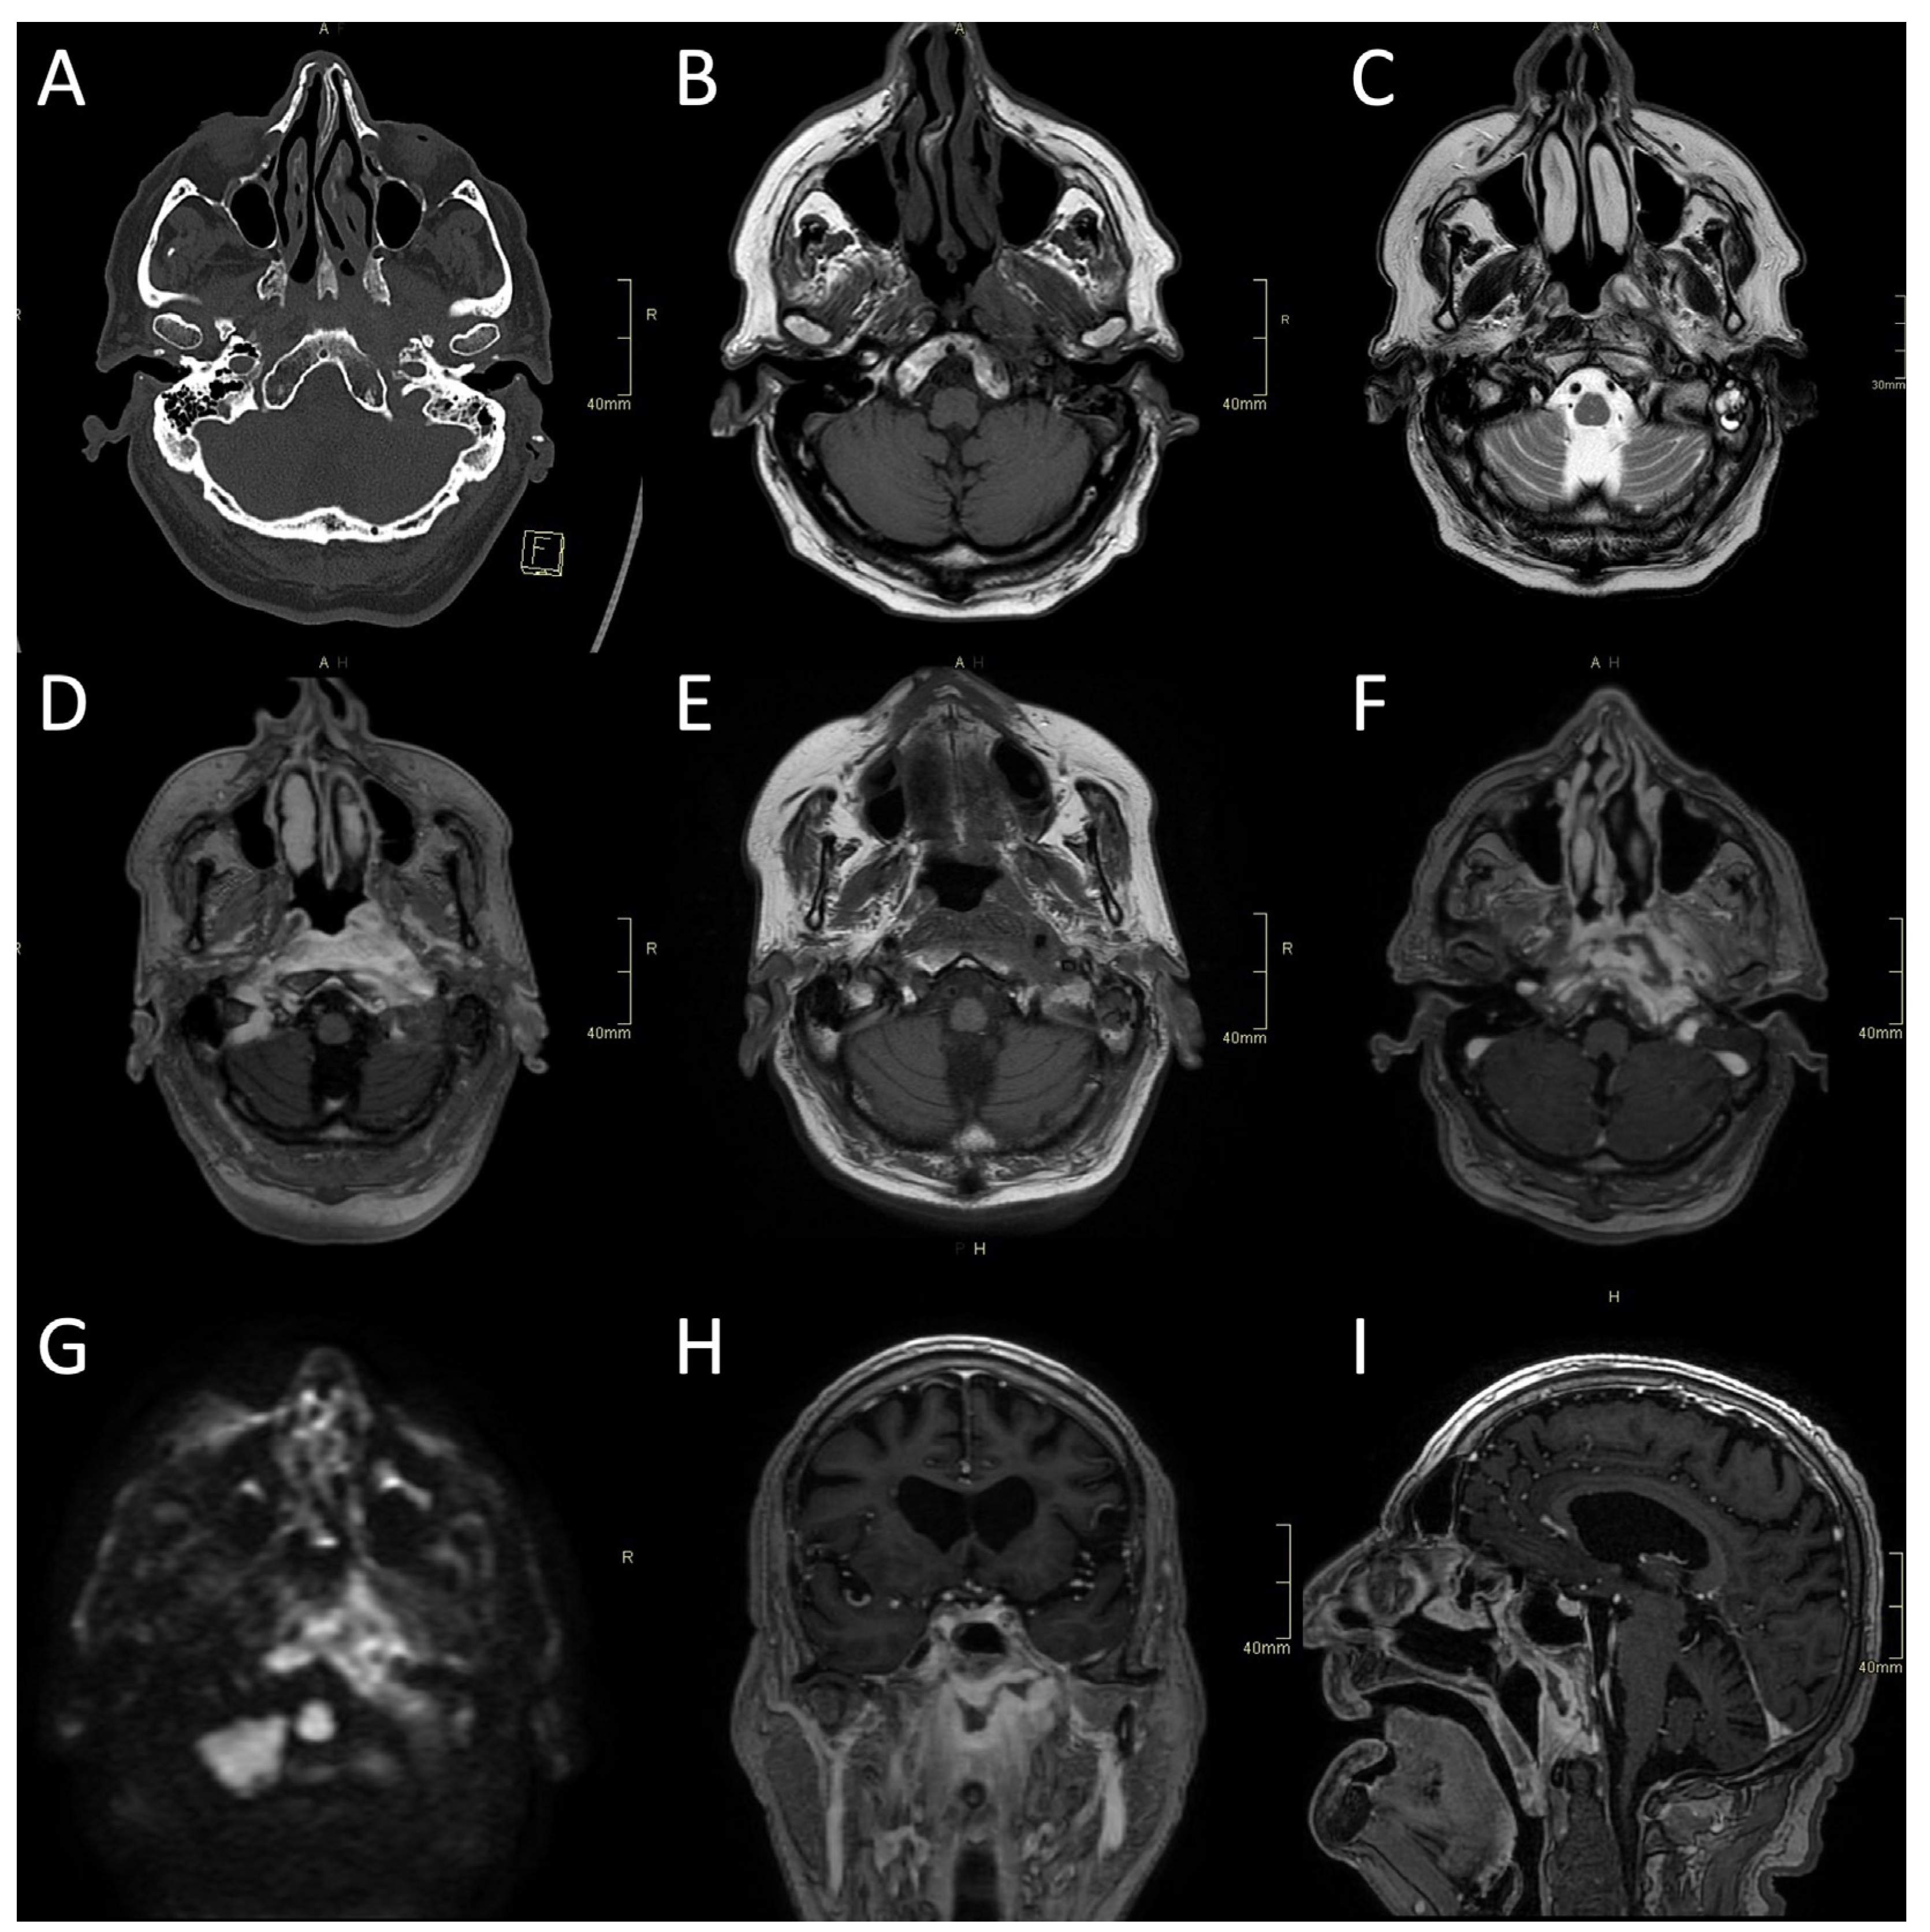

Figure 2.

CT and MRI of a fungal atypical skull-base osteomyelitis patient. (A) Axial CT bone algorithm reconstruction showing subtle cortical erosion of the left skull base and the left carotid canal; F—foot. (B) Axial MRI T1 showing subtle asymmetrical hypo-intensity, indicating oedema of the bone marrow on the left side of the clivus. (C) Axial MRI T2 showing asymmetrical hyperintensity in pharyngeal soft tissues and prevertebral muscles, indicating oedema and inflammation. (D) Axial MRI T1 showing the progression of oedema of the bone marrow of the clivus six weeks later. (E) Axial CE MRI showing the progression of hyperintensity in pharyngeal soft tissues and prevertebral muscles and affected bone marrow. (F,H,I) Axial, sagittal, and coronal CE MRI T1 showing extensive inflammatory changes in skull-base bone marrow and soft tissues, with non-enhancing branching fluid collection—abscess in the pre-clival and para/retropharyngeal soft tissues after 11 weeks. (G) Axial MRI DWI showing increased signal in the central skull base. CT: computerised tomography; MRI: magnetic resonance imaging; CE: contrast-enhanced; DWI: diffusion-weighted imaging.

CT is often the first imaging modality in patients with SBO as it is the most accessible and can be performed in the urgent setting. In addition, CT, especially high-resolution bone reformats, is the best way to assess the often subtle bone erosion and demineralisation characteristic of SBO [4,9,18,42]. Cortical erosions in ASBO are most often noted along the anterior clivus and foramina of the central skull base; in cases of invasive sinusitis, opacification and erosion of sinus walls can be noted, especially sphenoid sinus and ethmoid cells (Figure 1A, Figure 2A and Figure 3A,B) [6].

Typical for ASBO is symmetric pre-clival soft tissue involvement, producing nasopharyngeal swelling (Figure 2D,E). In addition, invasive sinus infections have a predilection for spread in the pterygopalatine fossa (Figure 3C,D) [4]. The infection of bone marrow in ASBO results in a loss of normal fat signal, which is seen as T1 hypo-intensity (Figure 2B) and STIR hyperintensity, with heterogenous contrast enhancement of the affected marrow [43,44]. Peripheral contrast enhancement is seen when an abscess is formed in the necrotic part of the bone marrow (Figure 2F,H,I). A combination of abnormal enhancement and absence of contrast enhancement is observed, particularly in mucormycotic infection, indicating the presence of inflammation and necrosis (Figure 4A,B) [45].

Imaging studies, both MRI and CT, including CTA and CTV, are essential in diagnosing complications of SBO. These include the intracranial spread of infection, the formation of an abscess, either intracranially (Figure 1B,D and Figure 4C,D) or in the soft tissues of the head and neck (Figure 2F,H,I), and vascular complications—venous thrombosis, venous or arterial stroke, and mycotic aneurism formation [30,46,47].